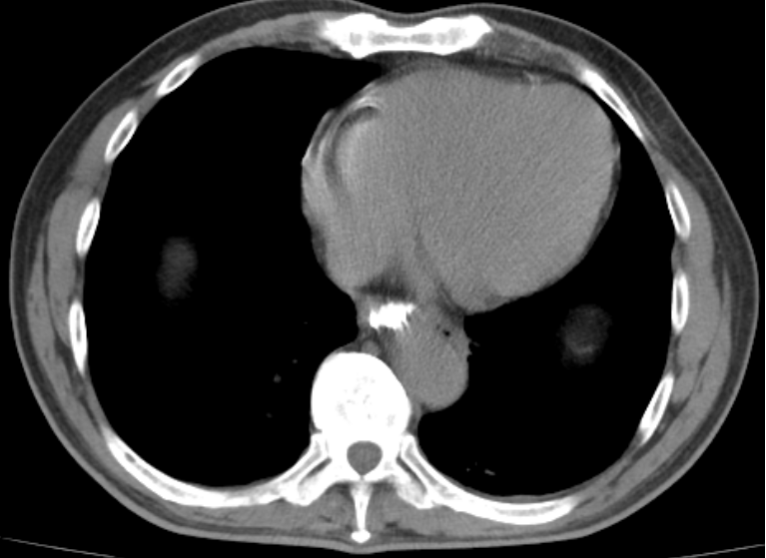

▲经过2周治疗后,复查胸部CT未见造影剂外溢

消化内科副主任医师黎俊及第二手术区副护士长刘晓静为患者进行急诊内镜下异物取出术。术中可见一枚枣核横跨在食管中段,其两端已经刺入食管左右壁,在食管穿孔局部进行吸引时,有大量脓液从穿孔处溢出。使用异物钳将枣核取出后,患者胸痛症状明显缓解。随后在内镜下放置鼻饲管及胃管进行引流,患者收入胸外科进一步诊治。在胸外科的细致诊治下,患者终于脱离险境,2周后复查胸部CT食管穿孔完全愈合出院。